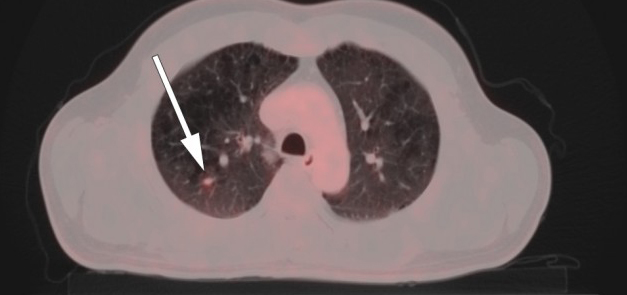

CT thorax viste uspesifikke små nodulære fortetninger i høyre lunge, den største med diameter 7 mm.

Lungekreft ble ikke påvist på CT thorax, men PET/CT helkropp viste malignitetssuspekte forandringer i høyre lungelapp og høyre hilus (fig 1). Cytologiske funn og biopsifunn fra lymfeknute i mediastinum bekreftet mistanken om småcellet lungekreft. Pasientens tilstand var forenlig med Lambert-Eatons myastenisk syndrom forårsaket av småcellet lungekreft ledsaget av cerebellær degenerasjon.